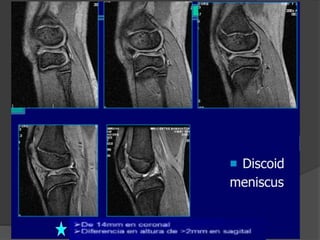

Menisco discoide

 Alteración congénita del desarrollo del menisco externo, es

la pérdida de la forma semilunar del menisco

 Esta anomalía los hace propensos a rotura

 El diagnóstico se realiza cuando se observa un

menisco marcadamente mayor que el menisco

normal.